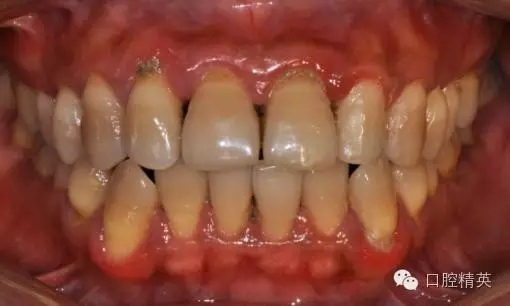

本病例 :女 34歲,主訴刷牙出血,覺(jué)牙齒輕度松動(dòng)一年。

檢查見(jiàn)大量齦上及齦下結(jié)石,探診出血,牙周袋較深,32-42 II度松動(dòng)。X線片顯示牙槽骨水平吸收。

診斷:成人慢性廣泛性中度牙周炎。

治療前: